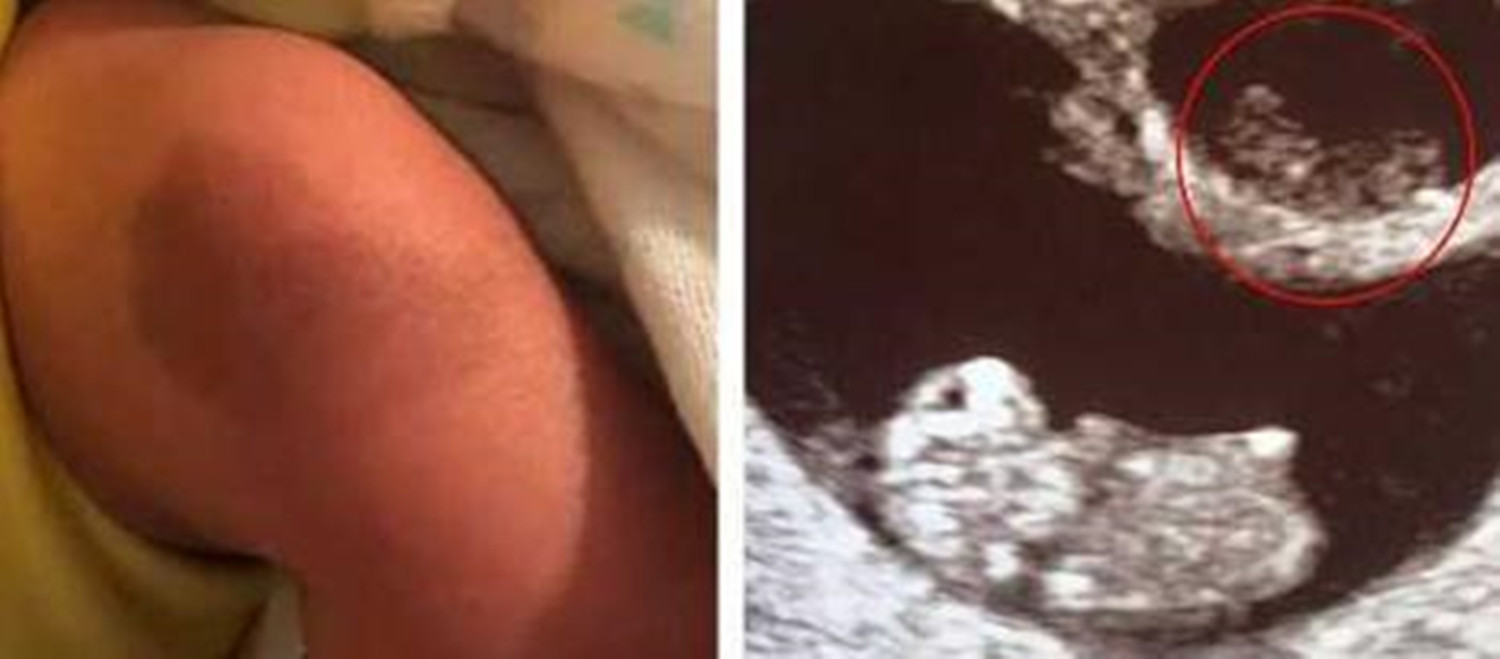

据《每日邮报》2月11日的报道,一名叫吉文斯的美国女子于今年初产下的儿子,腿上膝盖处存在一块胎记。

这块胎记有什么值得称奇的呢?原因在于其形状,与新生儿的龙凤胎姐姐孕期拍下的B超影像高度相似,下面跟大家说说细节。

好在最后龙凤胎中的弟弟健康降生了,更令她惊喜的是,当护士抱着孩子到她跟前时,还特地指了这块腰果状胎记给她看,形状和被“吸收”的姐姐的B超影像十分相似。

吉文斯既惊讶,又感觉得到了慰藉,心想这可能是未出生的姐姐给弟弟留下的一种特殊回忆吧。

弟弟出生后腿上的这块胎记,引发了众多关注,对这种奇妙的巧合,网友评论道:

- 这是最美胎记了吧?姐姐以另一种形式和弟弟一起生活下来了。